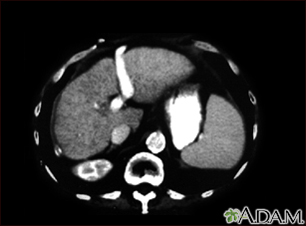

Liver cirrhosis - CT scan